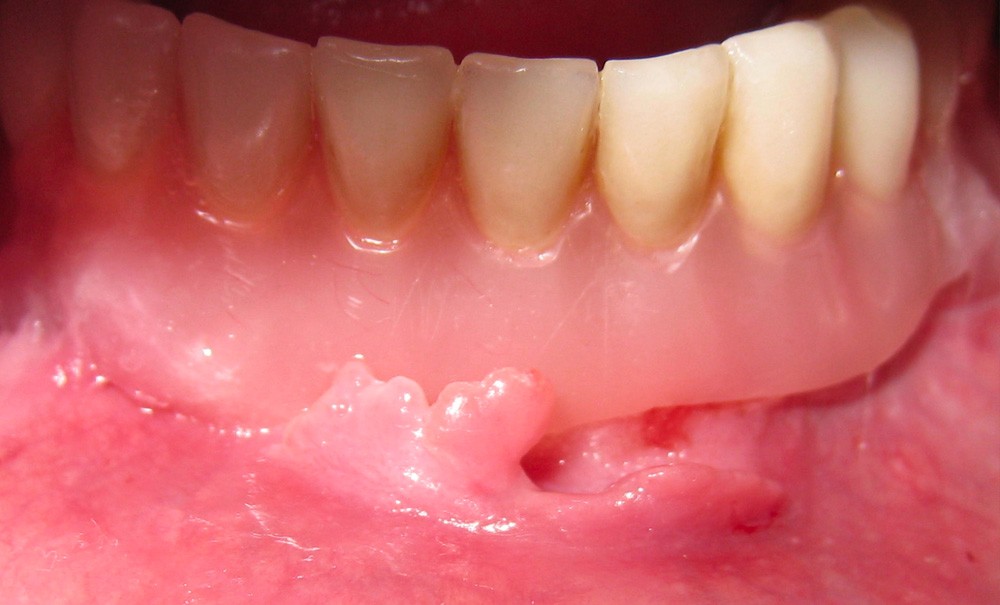

Un homme âgé de 72 ans, suivi pour une hypertension artérielle équilibrée, est adressé pour avis. Il présente une lésion muqueuse hyperplasique vestibulaire inférieure, en regard d’une prothèse adjointe complète (PAC) (fig. 1) réalisée dix ans auparavant environ. Il se plaint d’instabilité de sa prothèse complète. L’examen exo-buccal ne révèle aucune adénopathie cervicale. À l’examen endo-buccal, on note une hyperplasie muqueuse oblongue d’environ 15 x 4 mm, sans ulcération ni induration, qui vient « épouser » la selle prothétique de la PAC. L’orthopantomogramme ne révèle aucune image pathologique sous-jacente. L’examen occlusal au papier à articuler bleu montre une surocclusion prémolaires-molaires gauche.

Le diagnostic d’hyperplasie sous-prothétique (epulis fissuratum) est évident devant une hyperplasie « épousant » la selle d’une prothèse complète inadaptée. Le carcinome épidermoïde en l’absence de saignement au contact, d’ulcération, d’induration et d’adénopathie cervicale est écarté. Le granulome pyogénique (botryomycome) et le condylome acuminé ont des aspects caractéristiques, respectivement bourgeonnant vasculaire et papillomateux.